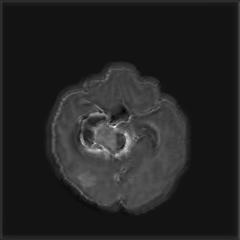

We argue that the sub-optimal paradigm of processing different abstractions within a single CNN pipeline can be remedied through the effective processing of information in a structured manner. Consequently, we devise strategies for disentangling the edge and texture information within a single training pipeline. Figure 2 illustrates how our proposed module, dubbed EG-CNN, can be paired with any existing CNN encoder-decoder to improve segmentation quality near intensity edges. We have applied our EG-CNN to the tasks of brain and liver tumor segmentation in medical images (Figure 3).

(1) Brain MR (2) Liver MR (3) Liver CT (4) Lung CT